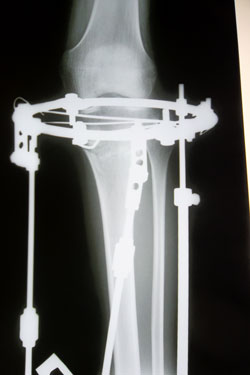

Дата операции 29.10.2013г.

Дата снятия аппаратов (с правой ноги) 07.02.2014г.

Дата снятия аппаратов (с левой ноги) 14.02.2014г.

Срок лечения 105 дней.